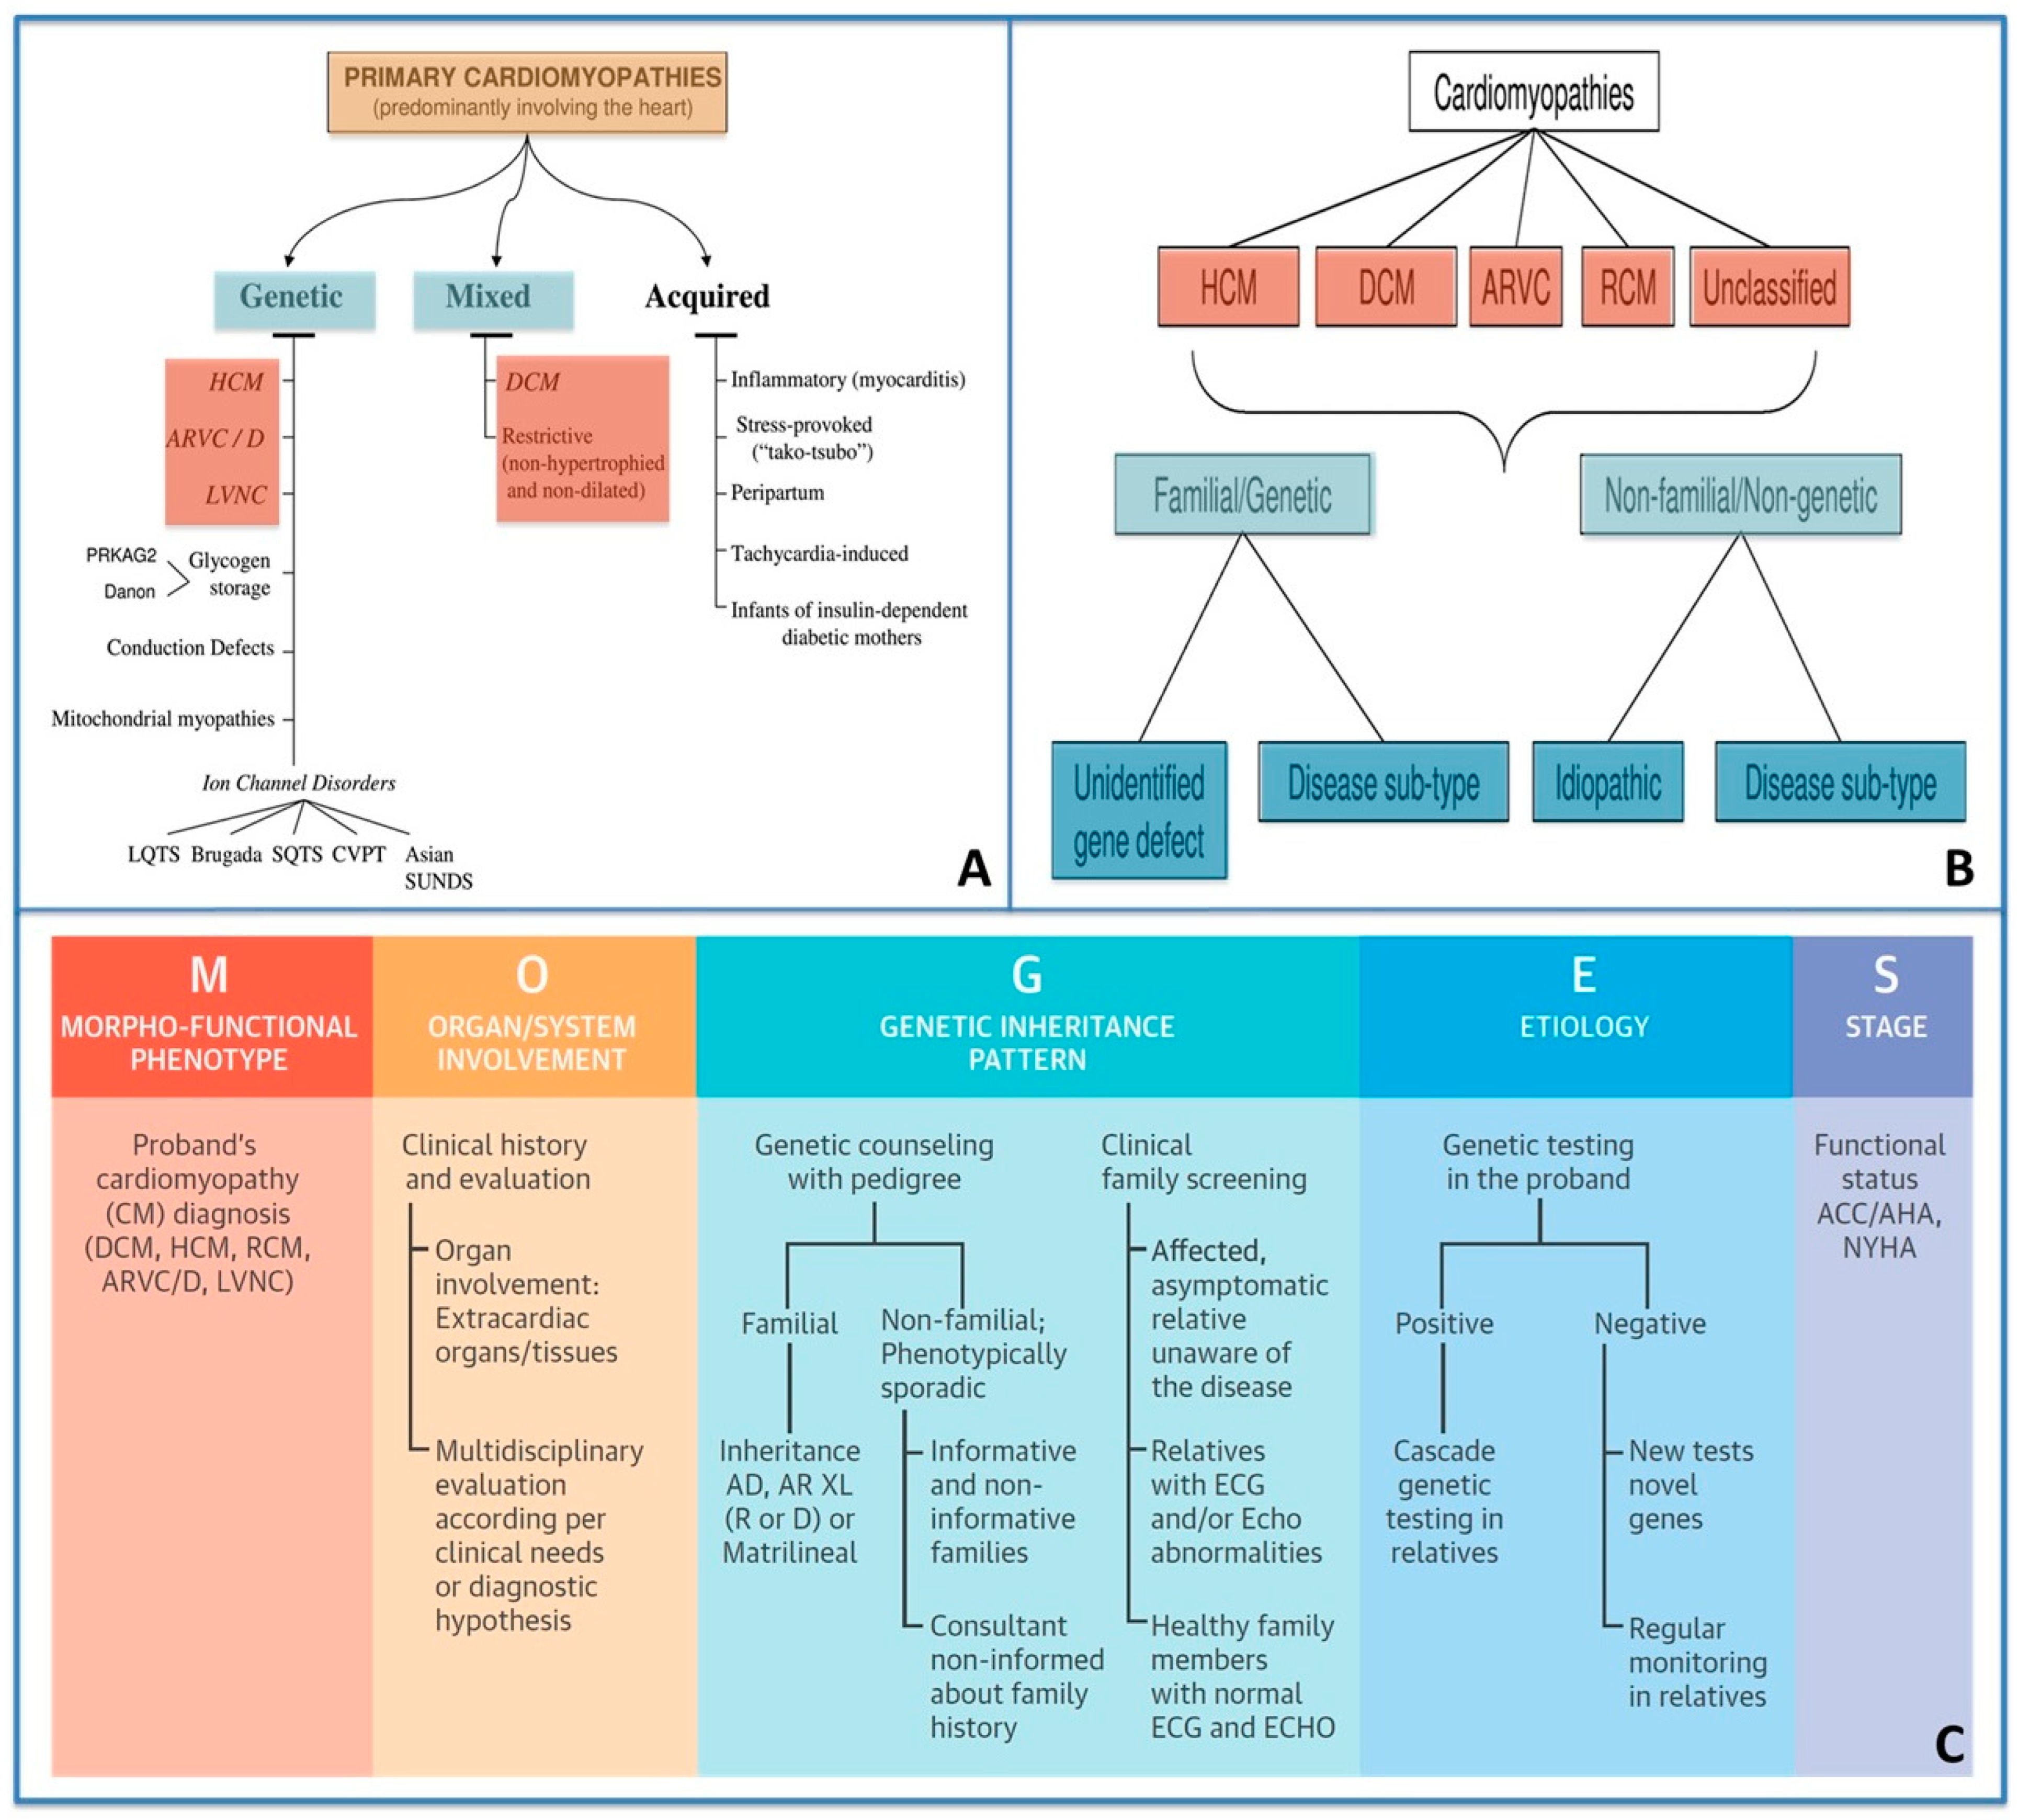

2. The Hierarchical and Multiparametric Approach of SCD Risk Estimation in Cardiomyopathies

2.1. Step 1: Clinical Evaluation and Family History (of CMPs and SCD)

2.2. Step 2: ECG and Echocardiography

2.3. Step 3: ECG Monitoring and Exercise Testing in SCD Risk Evaluation

2.4. Step 4: Multimodality Imaging in SCD Risk Evaluation

2.5. Step 5: Genetic Testing in SCD Risk Evaluation